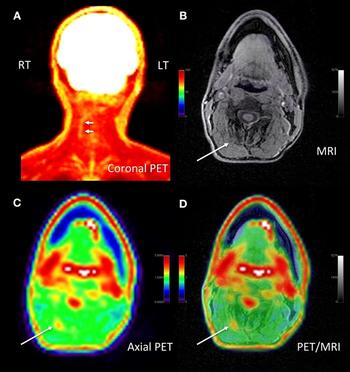

18F-FDG PET/MRI can identify pain generator locations, leading to changes in pain management.